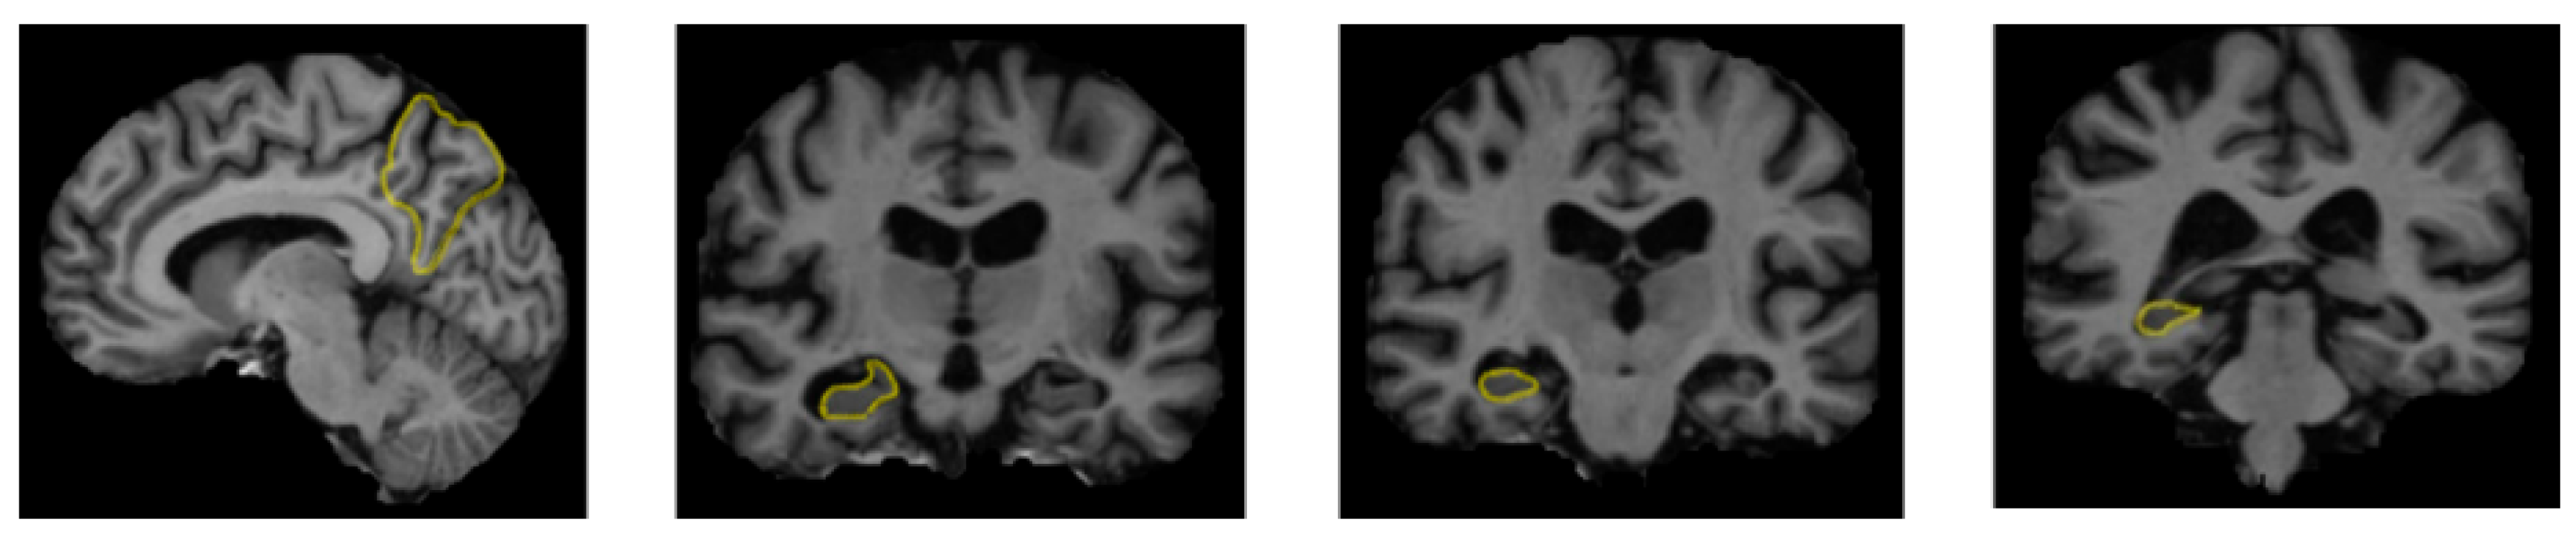

A range of influences affect the onset of Alzheimer’s disease, among them lifestyle choices, cardiovascular health, head trauma, age, gender, genetic predispositions, infections, environmental influences, and pre-existing conditions like diabetes, as depicted in Figure 1. In individuals with Alzheimer’s, abnormal protein formations such as amyloid plaques and neurofibrillary tangles develop in and around neurons in specific areas of the brain [29]. These pathological changes lead to the deterioration and damage of brain tissues, as shown in Figure 2 [30].

Figure 2.

The regions of the brain affected by Alzheimer’s disease in MRI images [30].